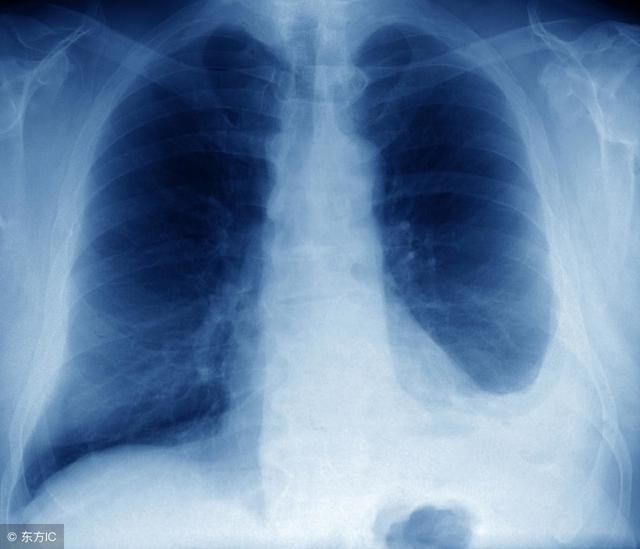

胸膜腔作为人体中一个完整封闭的腔隙,在正常情况下,其往往会存在有13-15ml作用的浆液,辅助着器官功能的运行。但是,一旦机体的正常平衡被打破,此时就有可能会出现过多液体集聚的异常情况,即人们常说的胸腔积液疾病。那么,该疾病的表现形式究竟都有什么呢?

其实,影像学检查也是临床上常用的诊断和评估胸腔积液的手段。相比较之下,影像学检查这一方式既不会造成患者机体的创伤,同时又具有较高的安全性。因此,对于临床患者而言,是一种值得考虑的检查方式。